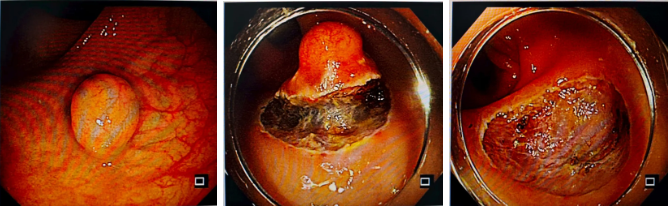

結腸脾曲早癌,ESD完整剝離

面對結腸脾曲早癌,精準定位病變范圍,完整剝離病灶,術后患者恢復良好;